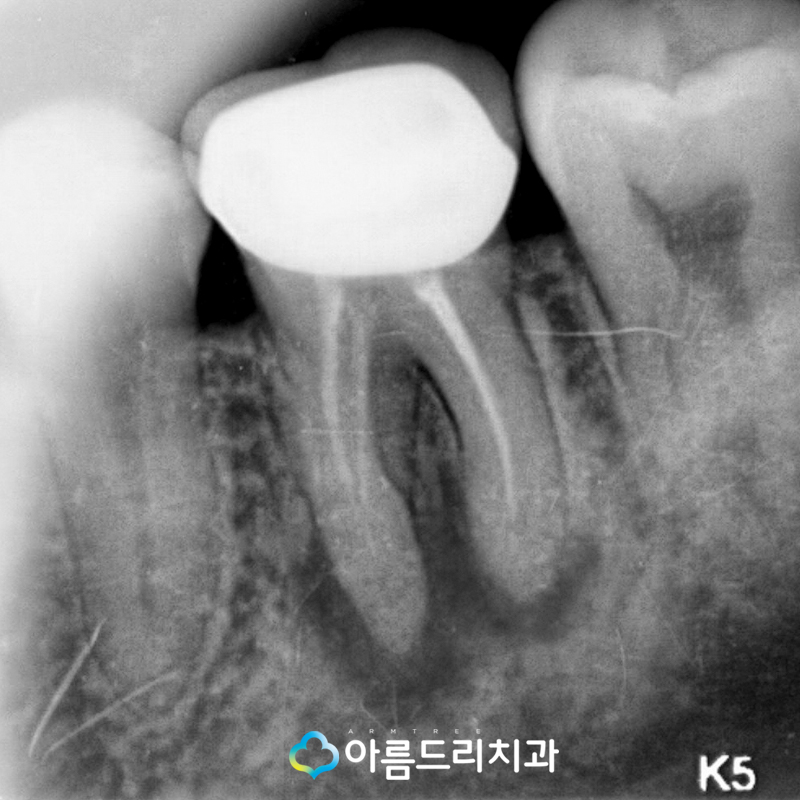

우선 치료를 받았던 치아의 잇몸쪽에 문제가 있는 것으로 파악하고 X-ray를 찍어봤습니다.

치근단 X-ray를 확인해본 결과 어금니 쪽 아래 부위가 다른 곳과는 다르게 검게 변한 상태로 치아의 뿌리쪽에 문제가 있어 염증이 발생하여 잇몸에고름이 나오는 증상의 잇몸고름주머니 가 생성된 것으로 확인할 수 가 있었습니다.